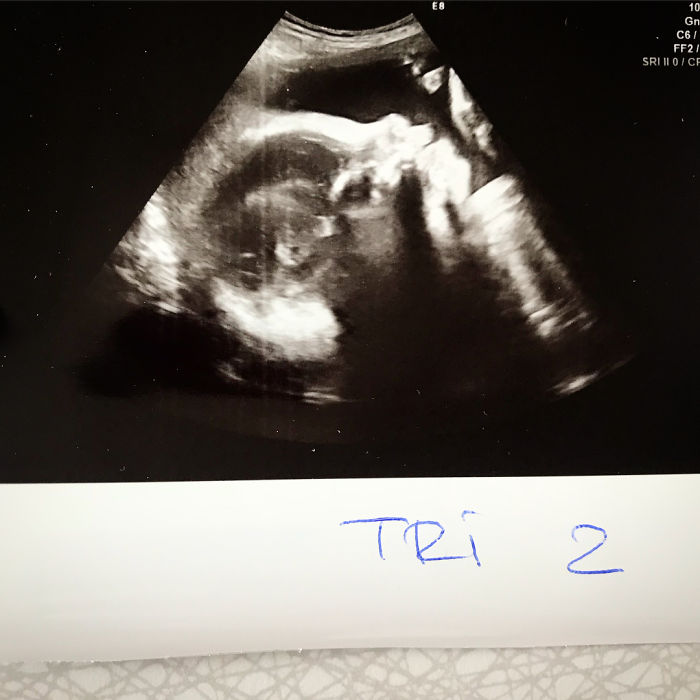

She has also shared a timeline of the incredible growth of her baby bump

“I’m glad we took these pictures. This <…> really shows the massive growth. It’s strange to have ended up with such a big belly and it’s even stranger that it can stand out like that without falling down!”